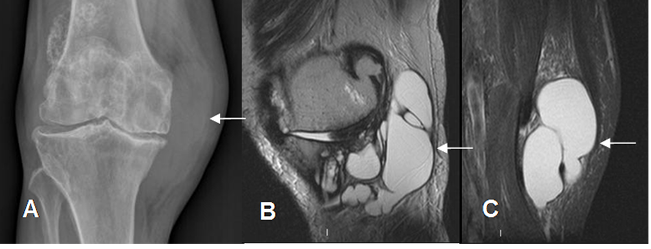

Fig 183. Bursitis anserina.

A: Rx AP. Prominencia de los tejidos blandos en la parte medial de la rodilla.

B: RM sagital en T2 y C: RM coronal en STIR. Imágenes quísticas que desplazan los tendones de la pata de ganso, por bursitis.